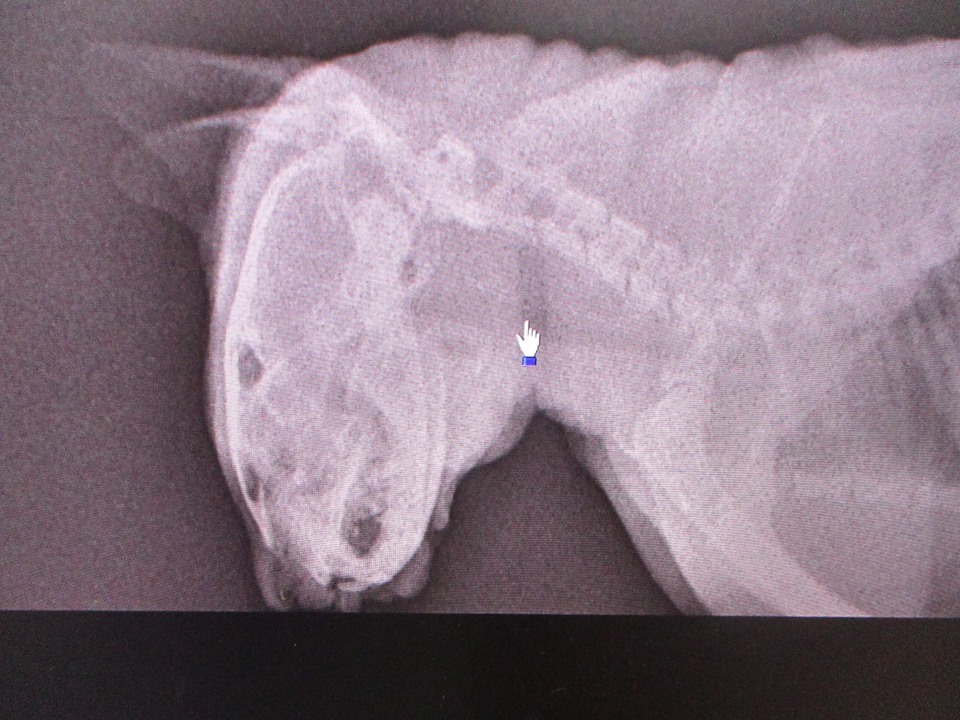

主題: 左眼感染失明之公白貓 申請者姓名: 許桂菱 花色: 申請日期: 2017-12-22 23:11:29 申請者部落格: 申請者臉書網址: 所在縣市/合作醫院: 彰化縣/成愛動物醫院 治療費用: 12950元 需求人數: 28人 已結案 (2024-06-01 13:20:33) 報名人員: Sophia x10(已付款)、meemee(已付款)、Karen(已付款)、林廷軒(已付款)、CharleyC(已付款)、devin(已付款)、f43067(已付款)、Sky Lin(已付款)、Norman Wu(已付款)、Ingham Kao(已付款)、mia(已付款)、kaede(已付款)、心桓、心桓 x2(已付款)、小奧 x4(已付款)、yoie(已付款)、 候補人員: 動物病情說明: 原本只是抓紮中途貓屋附近的街貓節育,結果目標母貓沒進籠反而抓到這隻沒見過的公貓,於是就順手帶去醫院做結紮,拍照時仔細一看卻發現左眼異常,沒了眼珠還發炎化膿,且頭部因疥癬抓傷,在不確認眼睛受傷的原因,於是照X光檢查後排除是外力造成,醫生建議因內部還發炎,先縫合眼尾,待發炎情況改善後再進行眼頭縫合,且生化血液及二合一快篩後有貧血及貓愛滋!